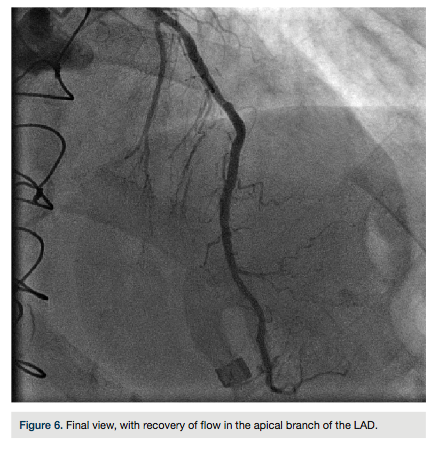

Wiggle wire (Abbott Vascular) and then we predilated with a 2.5 x 15 mm Angiosculpt (AngioScore) balloon. A 2.5 x 32 mm Promus drug-eluting stent (Boston Scientific) was advanced, covering the entire lesion length, and deployed at 12 atmospheres, then re-inflated to 14 atmospheres (Figure 5). Final angiography revealed TIMI-3 flow. The patient became bradycardic and subsequent repeat angiography demonstrated distal embolization to the apical LAD with loss of distal branches. She was given an intracoronary eptifibatide (Integrilin, Millenium Pharmaceuticals) bolus. Repeat angiography demonstrated recovery of flow in the apical branch (Figure 6). The patient tolerated the procedure well and was asymptomatic

throughout the remainder of her hospital course. She was discharged the following morning.